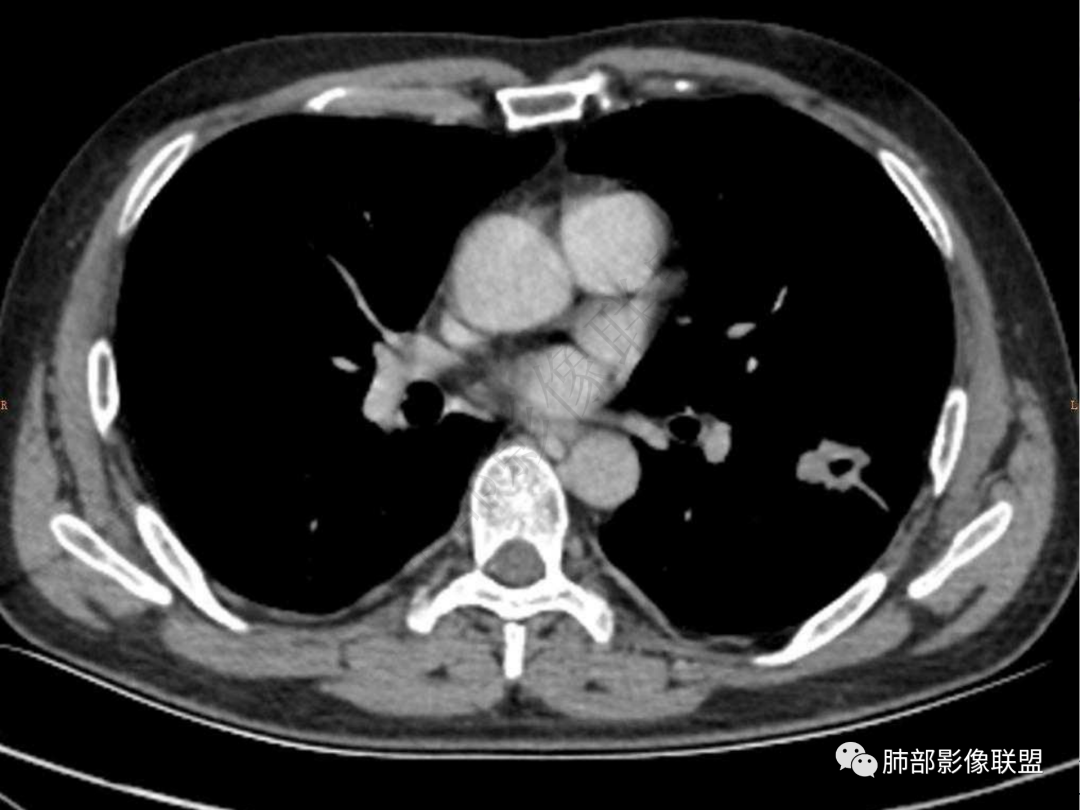

1.中年男性,咳嗽咳痰20余天,间断咯血2周

2.左肺下叶团片影,跨背段及内前基底段,实性部分类椭圆形,密度不甚均匀,可见毛刺及棘状突起,未见典型分叶及胸膜凹陷。病灶上下缘可见相应肺段支气管旁进侧出,管壁轻度增厚,未见狭窄阻塞。

4.实性部分不均匀环形强化并显示一小范围低密度坏死区或空洞。较之肺窗,整体纵隔窗范围较小,提示病灶并不十分密实。抑或为不同时段图像。

5.双肺门及纵隔未见增大淋巴结。未见胸腔积液。